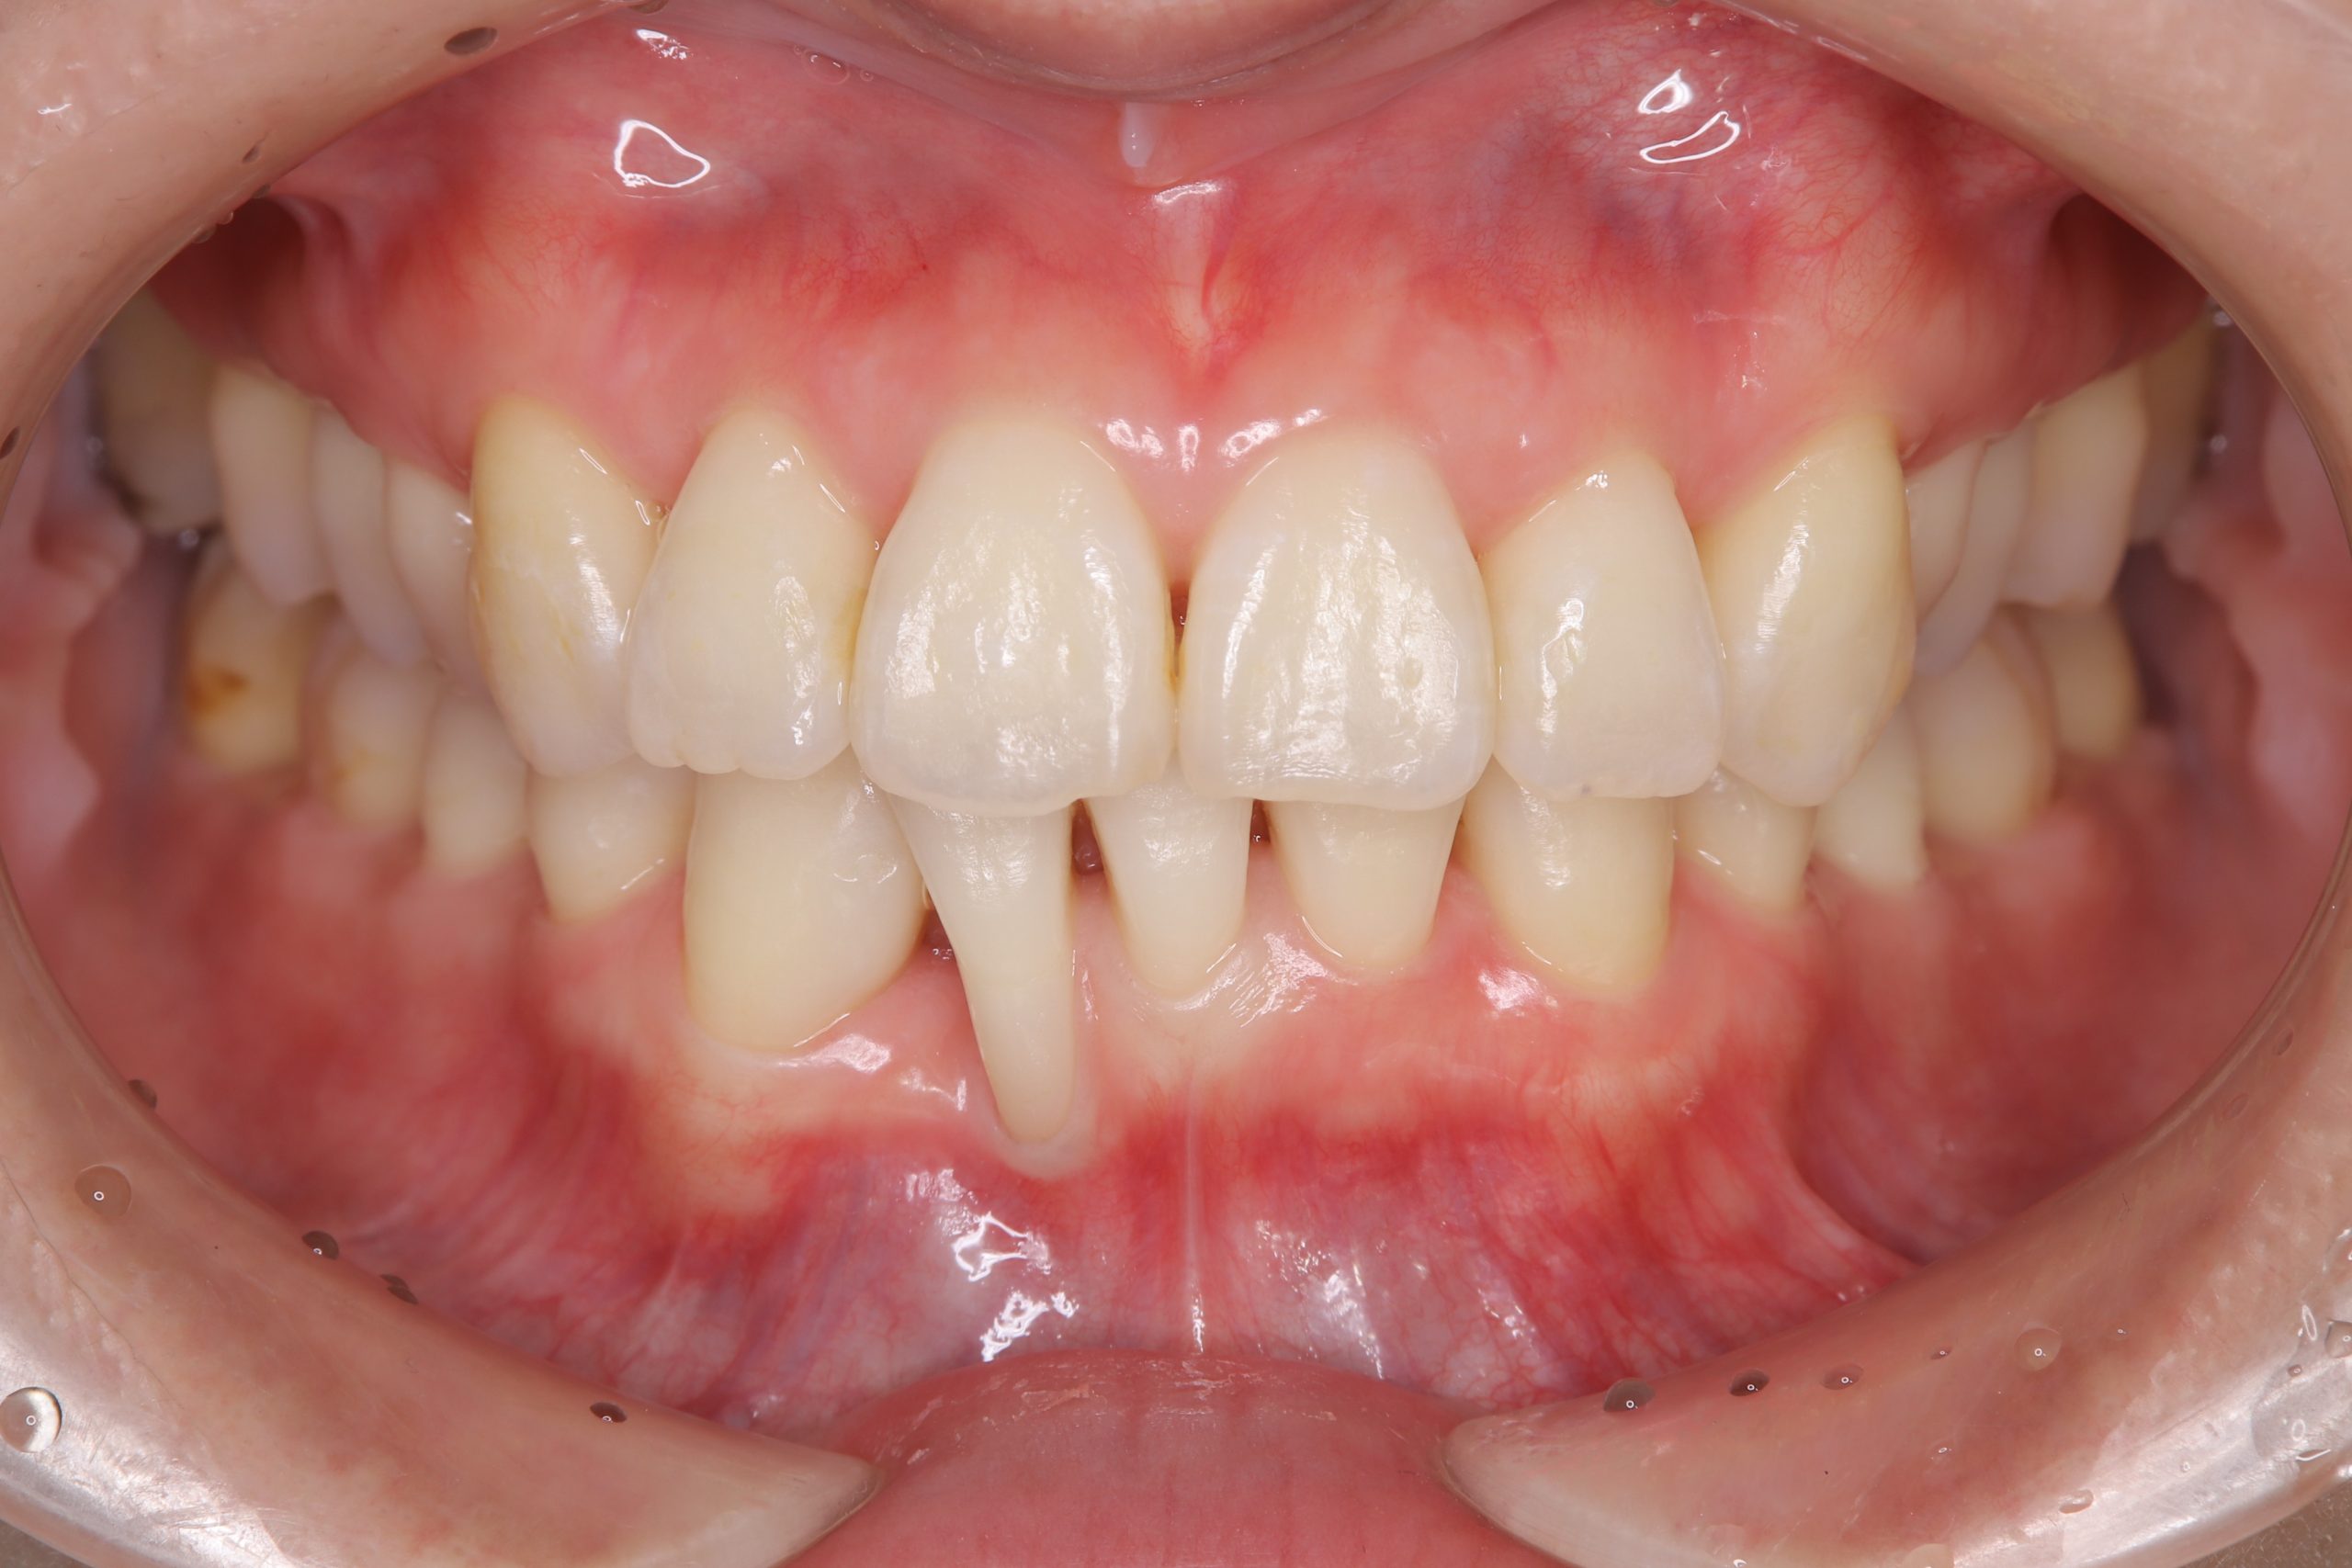

治療は、担当する歯科衛生士と連携を取りながら、SRP・むし歯治療・咬合調整・舌側に転位している右下2番(前歯)の抜歯・右下3番(犬歯)の近心スペース改善のダイレクトボンディング・ホームホワイトニング等を行いました。

現在は、SPT(メインテナンス)に移行し1年半程が経過しましたが、下の写真のように歯肉も歯も綺麗で、深い歯周ポケットもなく、良好に維持されています。

今後も、下の前歯の歯肉退縮が進行しないよう、噛み合わせや歯の位置、ブラッシングには注意していく予定です。